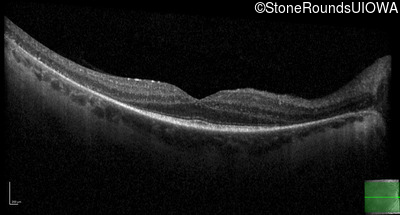

Age at visit: 44 years

OD OS